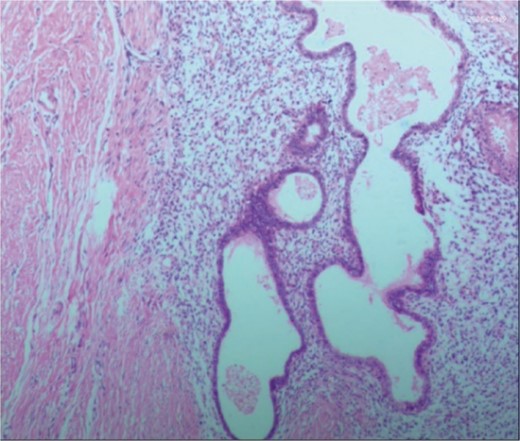

Postoperative pathology: the endometrial glands have typical stroma, blood, and macrophages containing hemosiderin.

PE represents a specific type of endometriosis, with related studies reporting that iatrogenic implantation is closely linked to the development of endometriotic lesions in perineal lateral incision scars [6]. PE exhibits symptoms similar to those of perianal abscesses, with both conditions originating around the anus. These conditions are clinically rare, often leading to misdiagnosis due to a lack of understanding among clinicians. In contrast to perianal abscesses, PE typically presents as recurrent perianal masses accompanied by cyclical pain, with the masses enlarging during menstruation and subsequently shrinking or disappearing thereafter [7, 8]. Patients often have a history of perineal lacerations or episiotomy, with surgical scars typically visible on specialized examinations. Anorectal examinations reveal no signs of anal sinus infection [9]. Ultrasonography demonstrates heterogeneous hypoechoic masses with punctuate or branching blood flow signals [10]. MRI exhibits a sensitivity of 90%–92% and a specificity of 91%–98% for the diagnosis of PE. MRI not only precisely locates the lesion but also outlines its extent, enabling differentiation from various anorectal conditions, thereby greatly aiding in the disease’s diagnosis [11]. Histopathological examination serves as the definitive diagnostic method for this condition, requiring the microscopic identification of two out of three components: endometrial stromal cells, glands, and hemosiderin, to confirm the diagnosis [12].